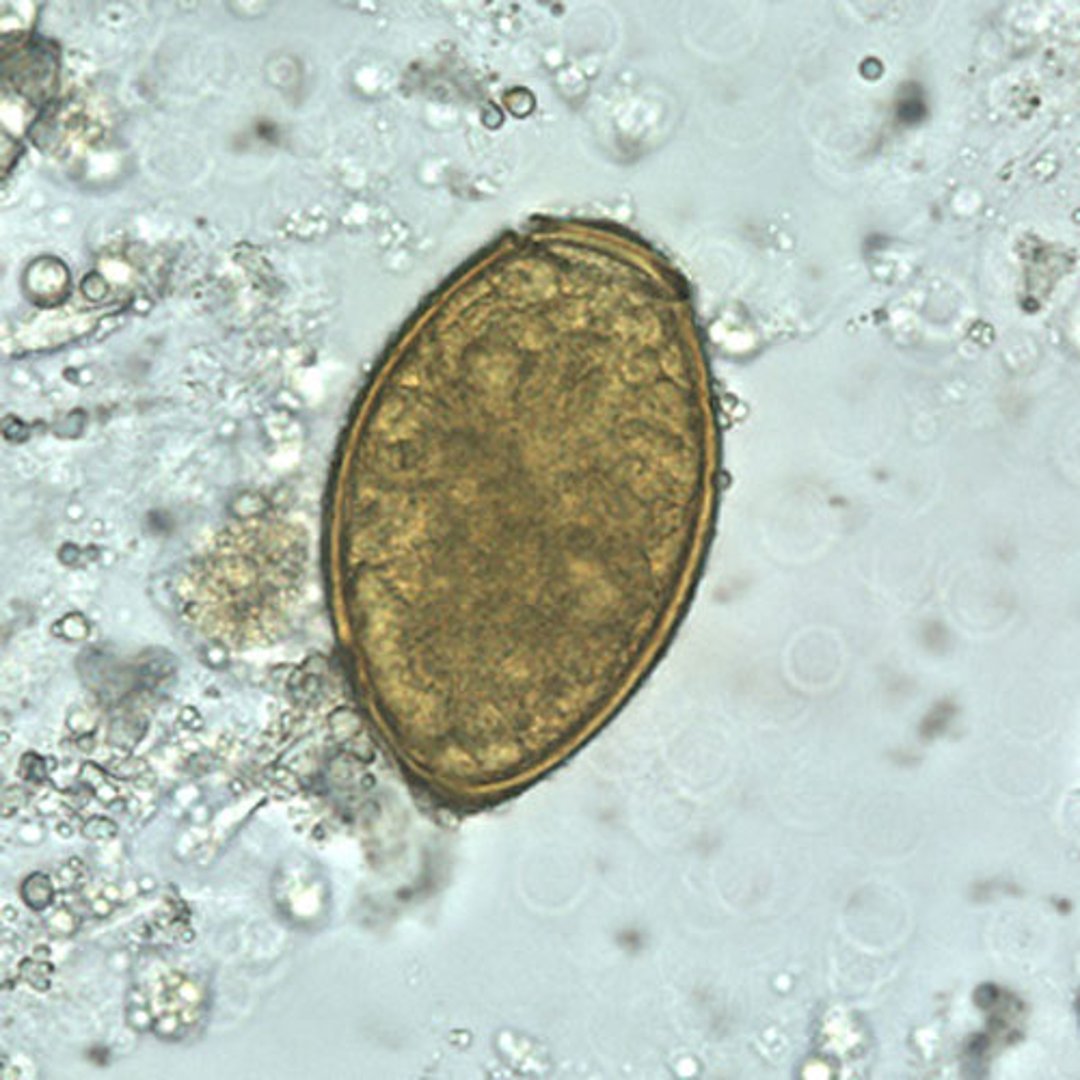

Paragonimus westermani-Ei

Die Eier von P. westermani sind zwischen 80 und 120 Mikrometer lang und zwischen 45 und 70 Mikrometer breit. Sie sind gelbbraun, oval oder länglich und haben eine dicke Schale. Die Eier sind oft asymmetrisch, wobei ein Ende leicht abgeflacht ist. Am großen Ende ist das Operculum deutlich sichtbar. Das aboperkuläre Ende ist verdickt.

Die Eier werden nicht embryoniert, wenn sie im Sputum oder Stuhl abgegeben werden.